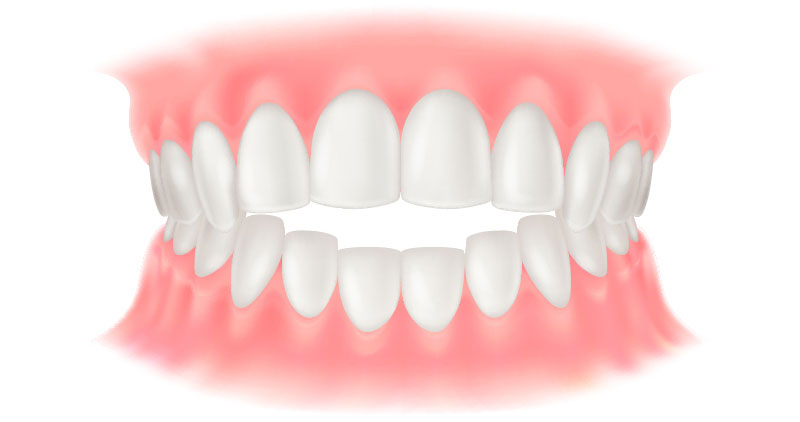

矯正歯科は、歯並びや噛み合わせを整える治療です。見た目の改善に加え、噛みやすさや磨きやすさが向上することで、むし歯や歯周病の予防にもつながります。また、噛み合わせが原因で歯周病が進行したり、歯が割れる、補綴物が壊れるといったトラブルが起きている場合には、その改善策として矯正治療を提案することもあります。

矯正歯科